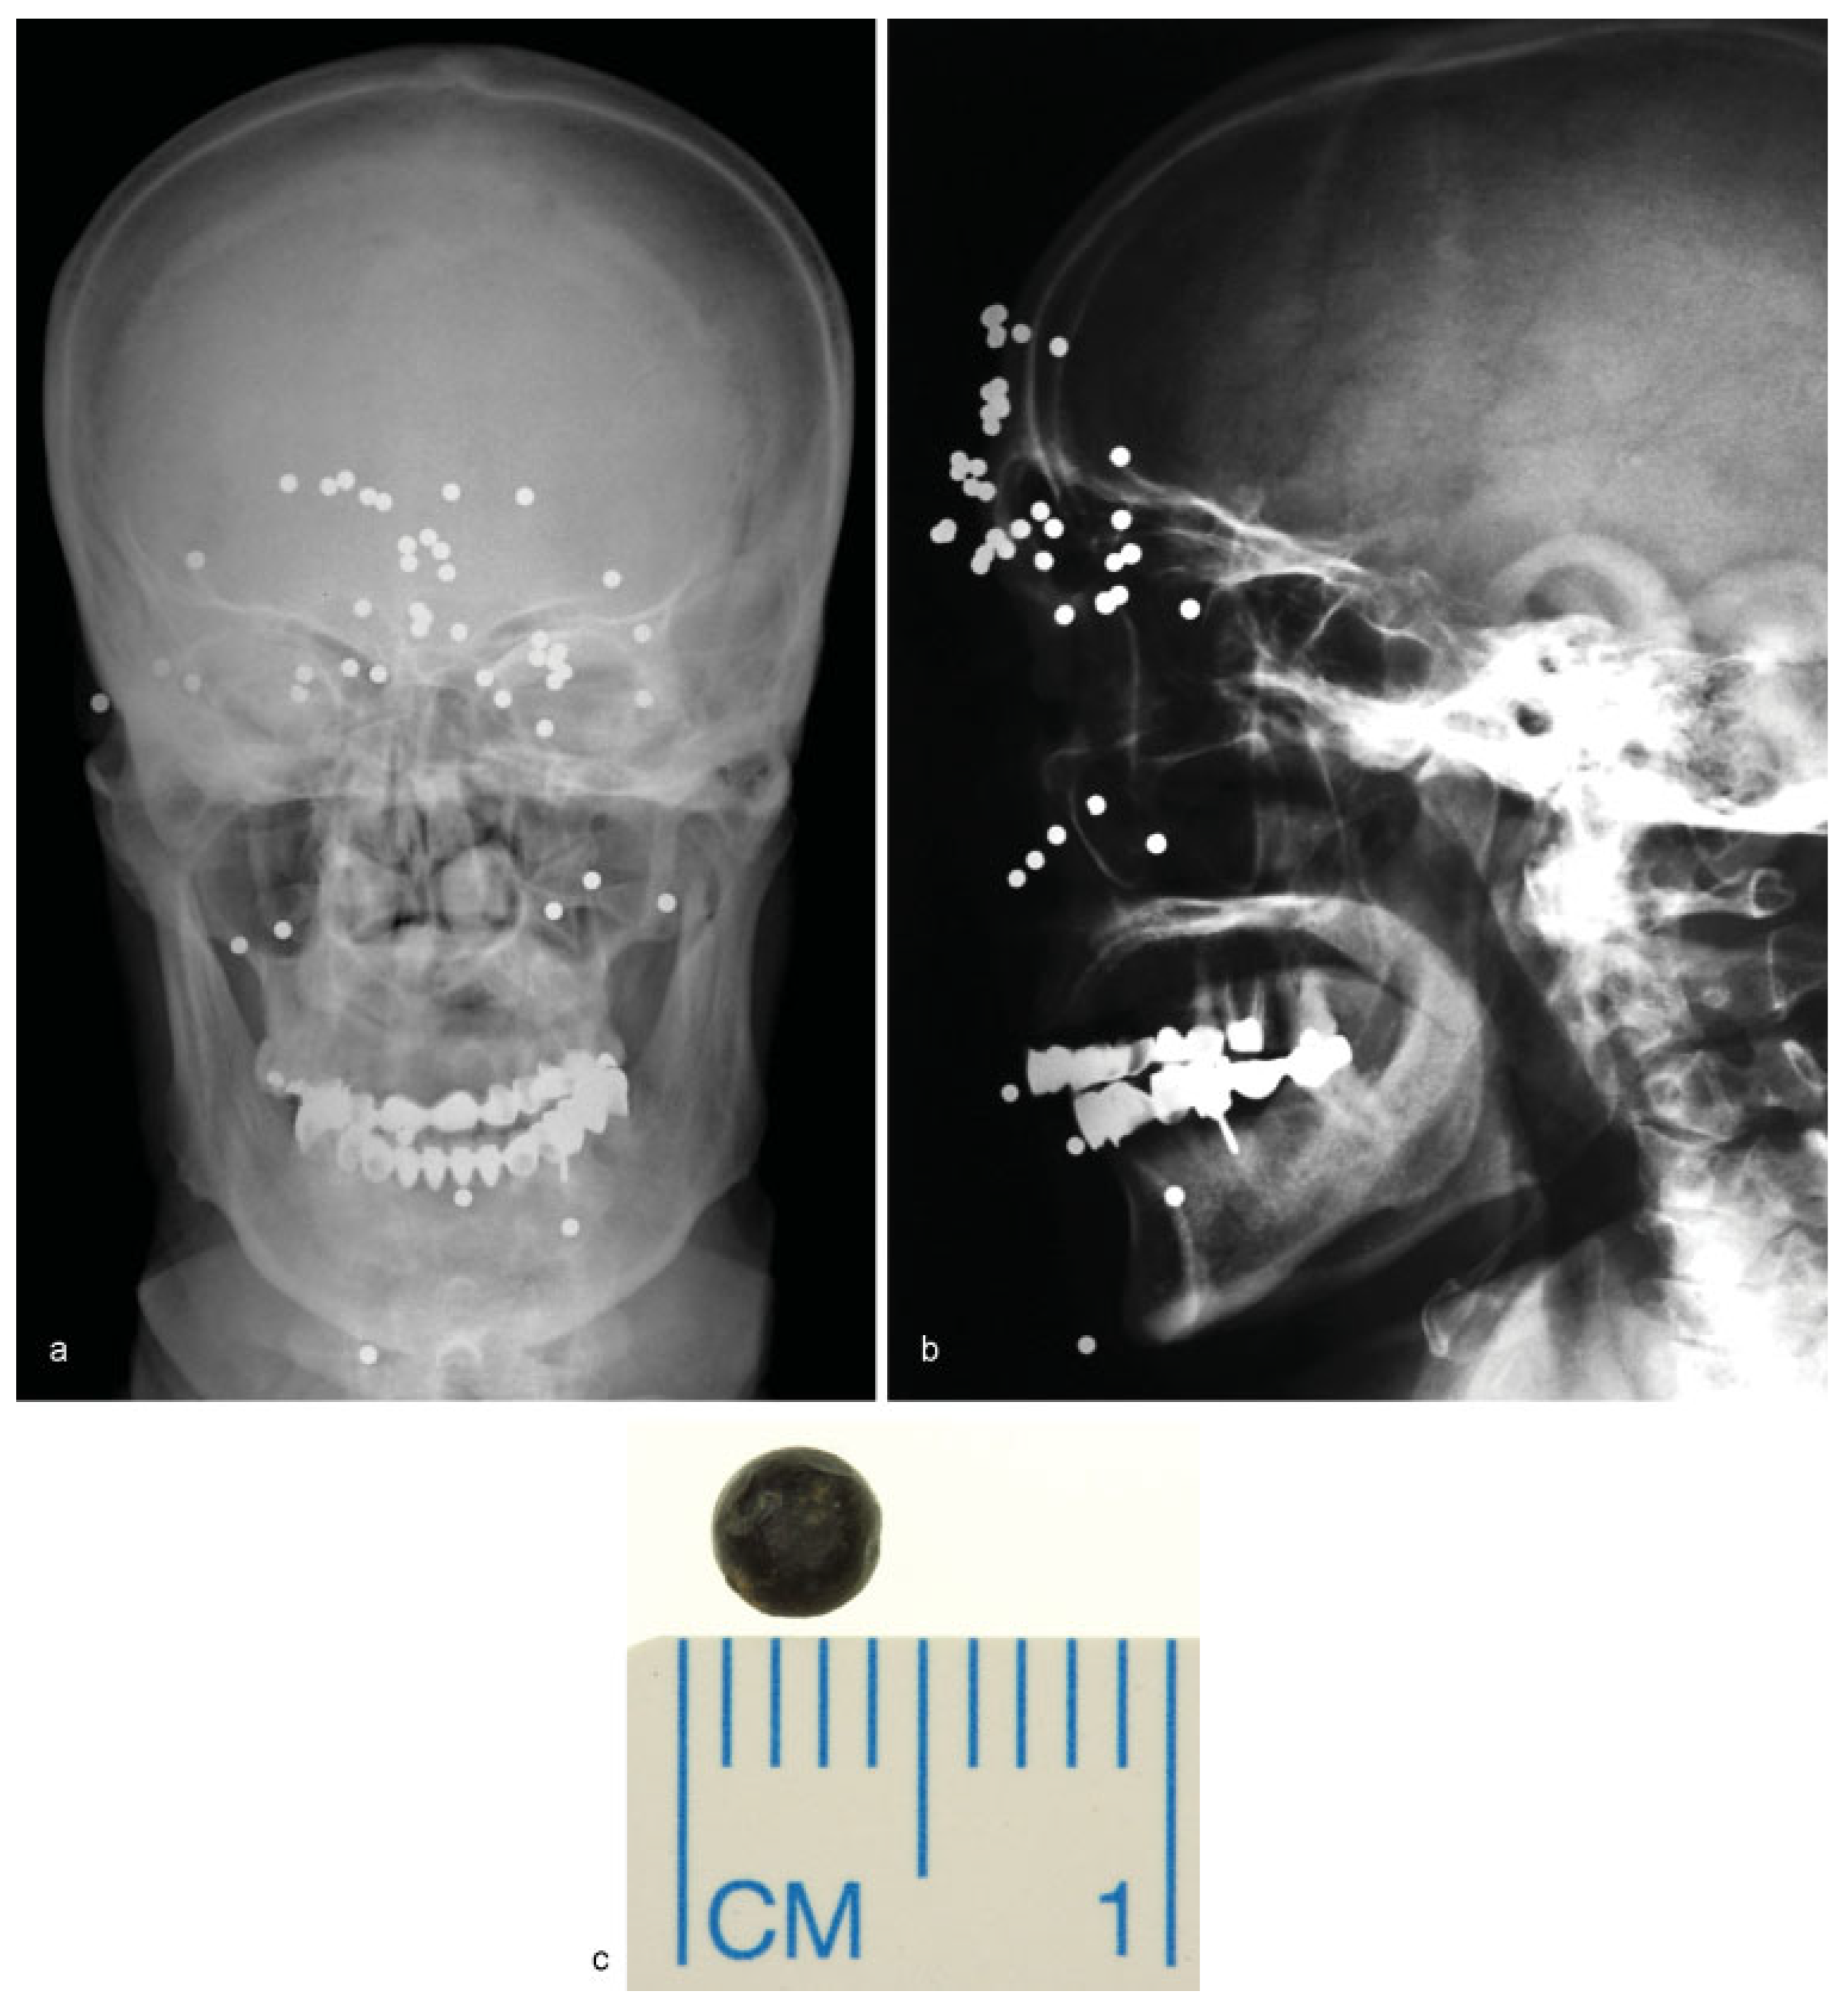

• Case 3: A 64-year-old patient shot himself by accident while handling a self-made rat trap in Turkey. Four days later, the patient travelled back to Germany on his own and visited the emergency department. Aside from multiple skin lesions, mainly around the periorbital region, clinical examination including ophthalmological assessment was uneventful, with the patient reporting only slightly blurred vision. Conventional X-ray demonstrated the presence of multiple shotgun projectiles throughout the soft tissue of his face (Figure 3a,b). In total, 46 projectiles were removed transcutaneously guided by intraoperative navigation and a C-arm X-ray, and assisted by ophthalmologists (Figure 3c). One projectile, located close to the superior orbital fissure, was left in place to prevent further damage (not shown). Postoperatively, the patient’s sight was undisturbed and healing proceeded normally. To our knowledge, no complications related to the remaining projectile have been noted.

Figure 3. (a,b) Frontal and lateral skull radiographs showing multiple radiopaque round foreign bodies spread over the face entering the orbital funnel. (c) Postoperative picture of a single shotgun pellet.